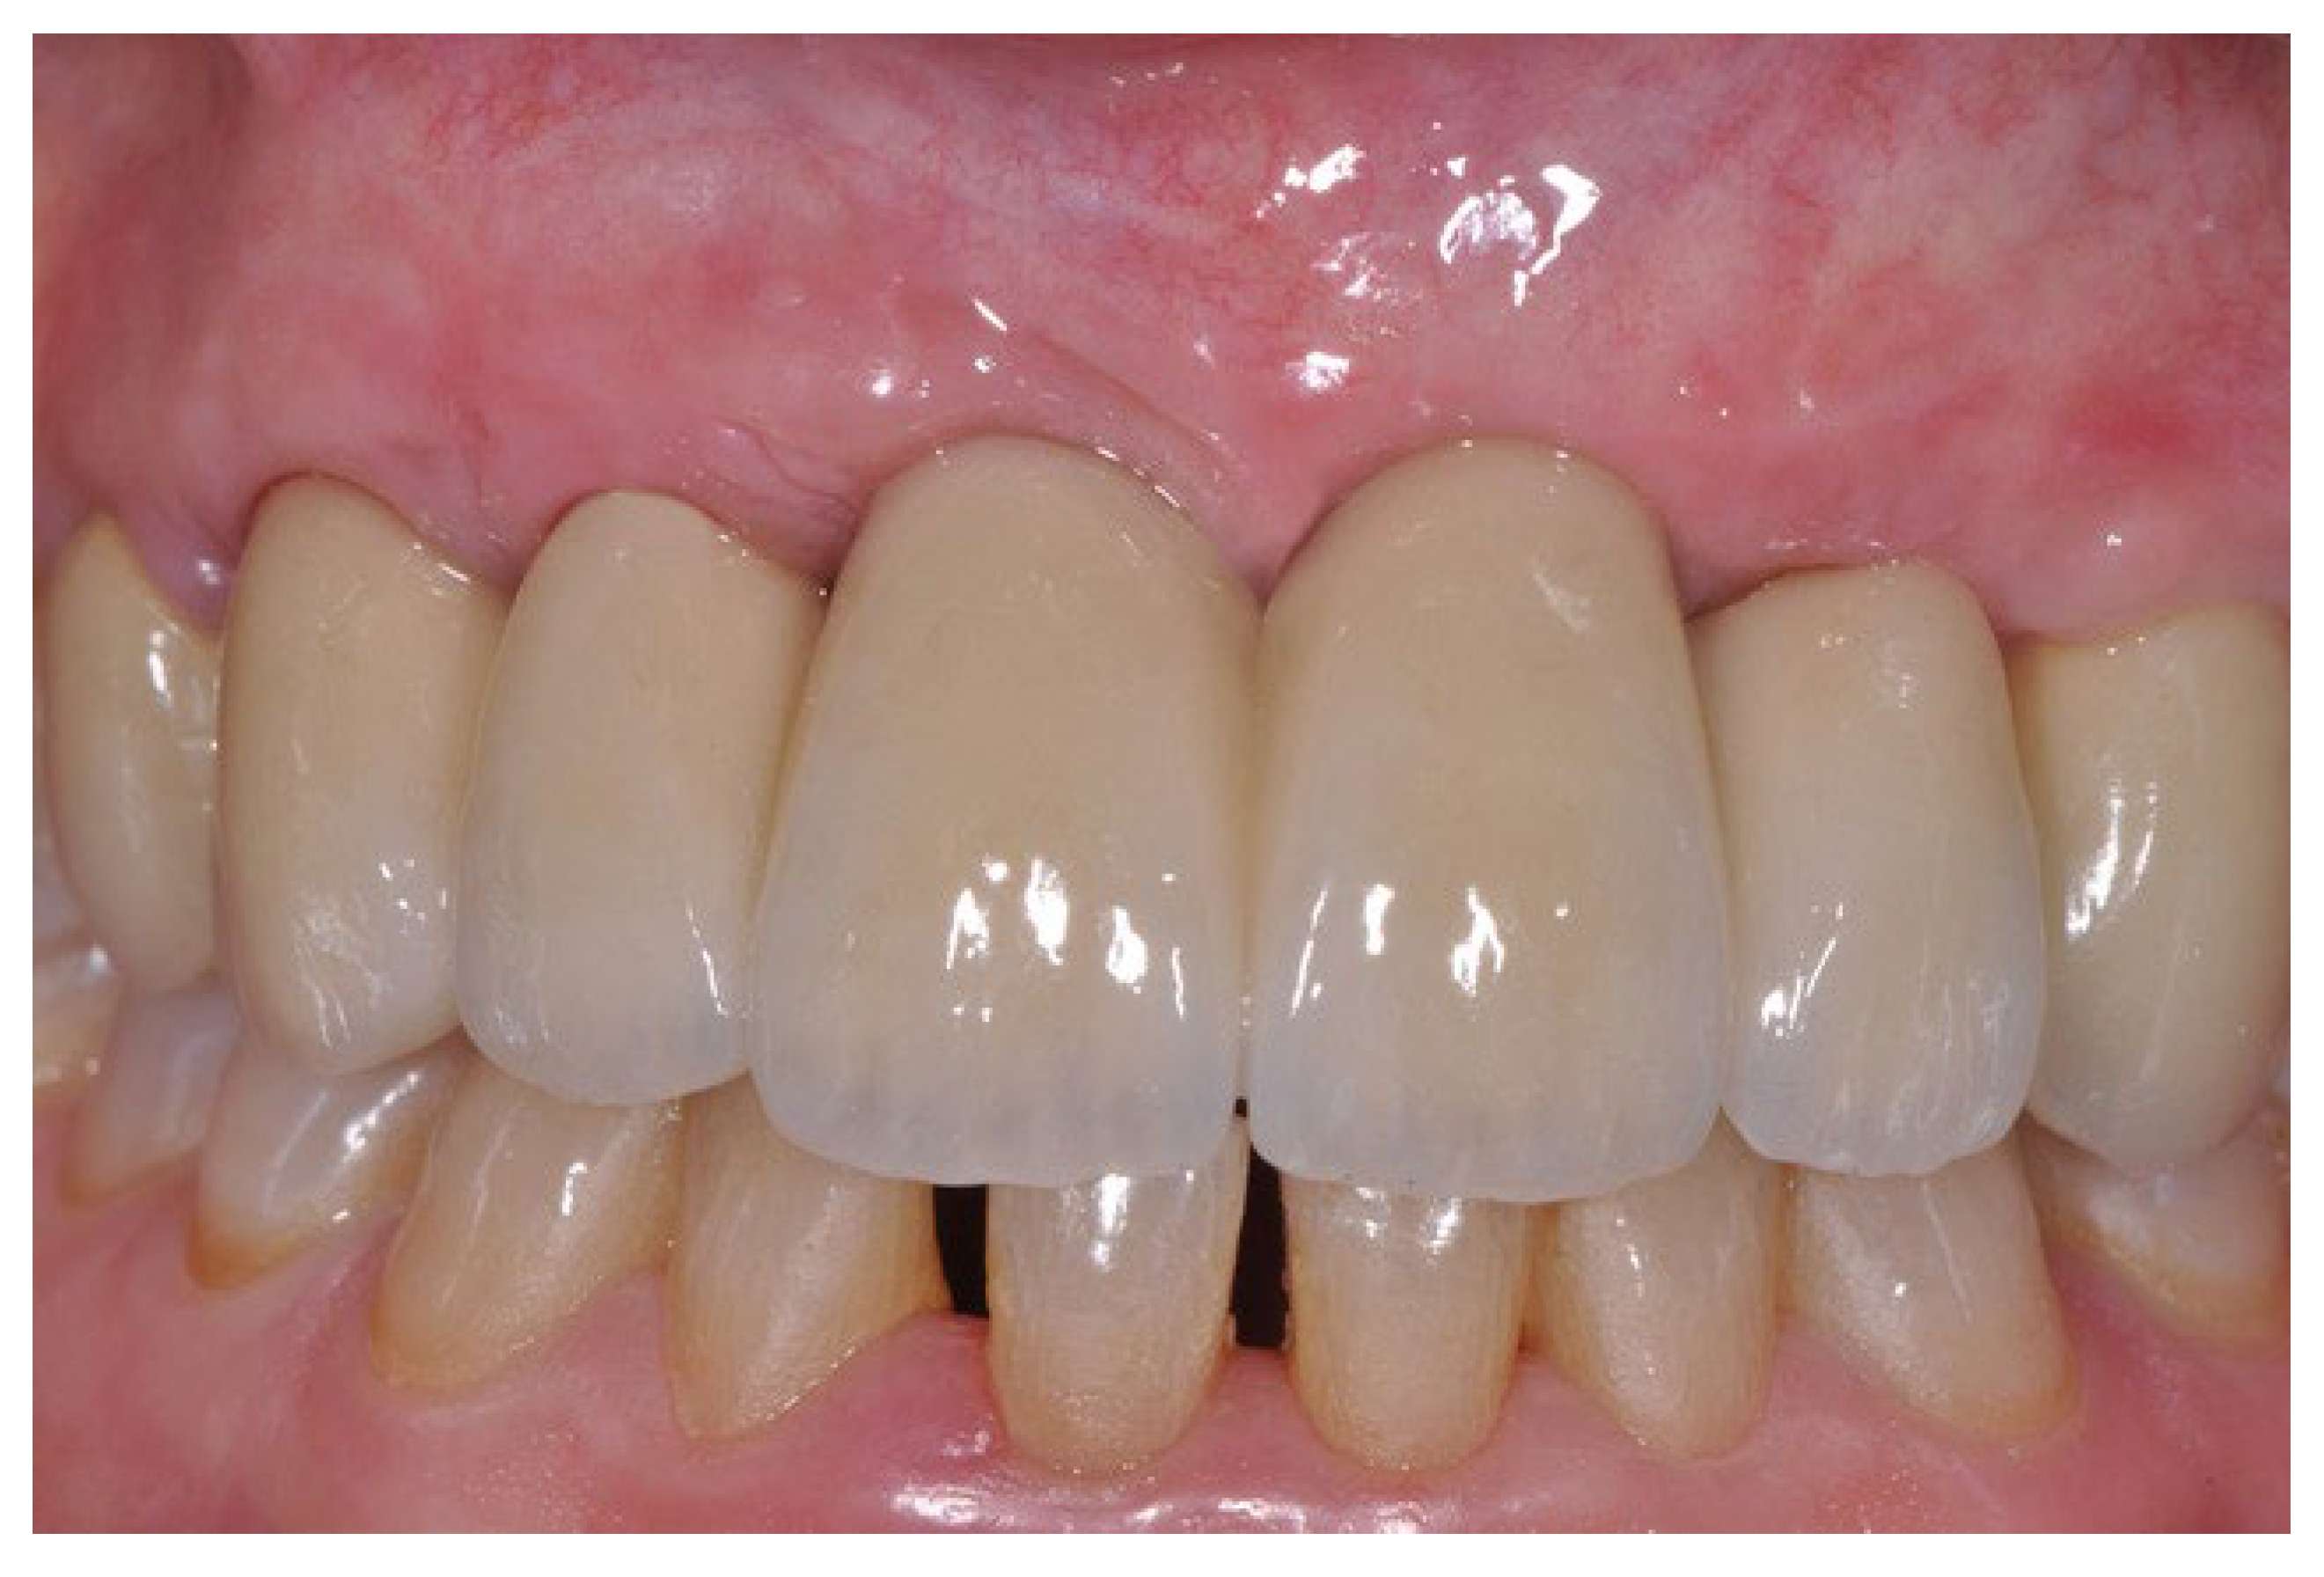

2. Methods

2.1. Case Presentation

2.2. Surgical Procedure

3. Results